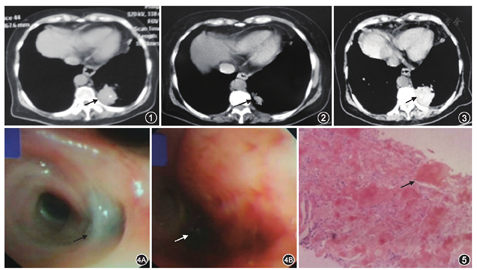

患者女,71岁。2018年10月2日无明显诱因出现咯血,鲜红色,总量约1 000 ml,伴呼吸困难,无胸痛、恶心、呕吐等症状,未予特殊处理。10月3日出现发热,体温最高达38 ℃,就诊于当地医院,查红细胞3.35×1012/L,血红蛋白102 g/L,血小板计数128×109/L;凝血酶原时间15.2 s,凝血酶原时间百分比64.2%。咯血原因待查,肺炎?肺癌?肺结核?支气管扩张?给予止血、消炎等对症治疗(具体不详),仍有间断咯血,为明确诊断,遂于10月4日就诊于我院急诊科。查血红细胞2.42×1012/L,血红蛋白76 g/L,血小板计数80×109/L;白蛋白28.6 g/L,钾3.19 mmol/L;凝血酶原时间19.9 s,凝血酶原活动度51%,D-二聚体652 μg/L;降钙素原0.84 μg/L;血气分析:动脉血氧分压77 mmHg(1 mmHg=0.133 kPa),动脉血二氧化碳分压33.1 mmHg。胸部CT平扫+增强示,左肺下叶支气管闭塞,远端各叶分支未见明确显示,左肺下叶后外基底段片状高密度影,其内类圆形低强化区,占位性病变不除外(图1)。为评估支气管动脉及其肺部病变,行支气管动脉血管成像(CTA)示,约第7胸椎水平降主动脉内侧壁发出一支血管,其分出一支肋间动脉,另一支走行至右肺门。咯血原因待查,肺炎?肺癌?肺结核?给予垂体后叶注射液(3 ml,静脉点滴或静脉泵入,共5次)、酚磺乙胺(15 ml,1次/d,静脉点滴,共4 d)、矛头蝮蛇血凝酶(2单位,2次/d,静脉注射,共4 d)止血、头孢哌酮-他唑巴坦(2.25 g/次,2次/d,静脉点滴,共4 d)抗感染、泮托拉唑纳(40 mg,1次/d,静脉点滴,共4 d)抑酸、氯化钾补钾对症治疗,咯血量逐渐减少,间断咯暗红色血块。10月7日再次突发咯血,量约500 ml,因内科治疗效果欠佳,给予左、右支气管动脉造影,左支气管未见显影,右支气管动脉增粗显影,逐个造影,选择至责任动脉,注入适量明胶海绵颗粒栓塞,栓塞后再次造影时栓塞满意,后咯血症状明显改善,为进一步明确诊断,于10月8日收入我院呼吸科。既往史:干燥综合征15余年,未治疗。入院体检:体温36.2℃,脉搏80次/min,呼吸19次/min,血压141/61 mmHg。神清语利,浅表淋巴结未触及,唇红,双肺呼吸音粗,左下肺可闻及湿啰音。心率80次/min,律齐,心脏各瓣膜听诊区未闻及病理性杂音。腹软,无压痛及反跳痛,肝脾肋下未及,双下肢无水肿。辅助检查:2018年7月6日因干燥综合征行胸部CT示,双肺间质性改变,双肺散在肺大泡;左肺下叶后基底段不规则团片状影伴钙化影,陈旧病灶可能(图2)。初步诊断:(1)咯血原因待查,肺炎?阻塞性肺炎?肺癌?肺结核?(2)干燥综合征。入院后给予酚磺乙胺(2 g,1次/d,静脉点滴,共8 d)止血、头孢哌酮-他唑巴坦(2 g,2次/d,静脉点滴,共22 d)、左氧氟沙星(0.4 g,1次/d,静脉点滴,共18 d)抗感染,氯化钾补钾治疗。治疗后患者无咯血,病情平稳。入院后完善实验室检查,结核分枝杆菌核酸检测阴性;结核抗体阴性;结核分枝杆菌抗原分析CFP10(-),LAM(-),ESAT(-),38 000(+),16 000(-);结核分枝杆菌T细胞检测阴性。癌胚抗原1.63 μg/L,癌抗原125(CA125)31.42 U/ml,癌抗原15-3(CA15-3)7.69 U/ml,甲胎蛋白4.41 μg/L,人绒毛膜促性腺激素0.96 mIU/ml,鳞癌抗原0.78 μg/L,神经元特异性烯醇化酶4.04 μg/L,细胞角蛋白19片段4.73 μg/L,糖链抗原19-9(CA19-9)17.86 U/ml,糖链抗原242(CA242)5.39 U/ml,结合型前列腺特异性抗原(C-PSA)0.52 μg/L,糖链抗原72-4(CA72-4)1.44 U/ml。红细胞沉降率90 mm/1h;IgA 6.53 g/L,IgG 28.31 g/L,轻链κ(KAPPA)5.48 g/L,轻链λ(LAMBDA)4.55 g/L;抗核抗体(+),抗SSA/Ro 60 000抗体(+),抗SSA/Ro 52 000(+);补体C4 0.12 g/L。为明确咯血病因,10月15日行正电子发射计算机断层显像(PET-CT)示,(1)左肺下叶后基底段空洞型肿块,临近少量胸腔积液,倾向空洞型肺结核可能。(2)左肺上舌段混合密度结节(图3)。因不能排除继发性肺结核可能,10月17日行气管镜检查示,左上叶后段支气管黏膜可见少许污秽色色素沉着,开口可见一腺体萎缩。左下叶后基底段一亚支内可见新鲜出血,吸引干净后远端可见一暗红色血块完全阻塞。余未见明显异常(图4)。因气管镜检查中未见肿瘤征象,未能取得活检,为进一步明确病灶性质,于10月22日行肺穿刺活检,左下肺活检组织病理显示,肺组织结构消失,大量炎性细胞浸润,大量均质红染无结构物质沉积,高度可疑淀粉样物质沉积。因我院病理科无法行刚果红染色,遂送至外院病理科,刚果红染色显示左下肺组织间质内见团块状粉染无定形物沉积,结合形态及特殊染色结果,符合淀粉样物质沉积(图5)。免疫组化,CD68(散在+细胞),Masson(±),刚果红染色(+),PAS(+)。因患者既往干燥综合征15余年,肺穿刺活检提示肺淀粉样变,故诊断干燥综合征继发支气管肺淀粉样变伴咯血。经支气管动脉栓塞术、抗感染、止血对症治疗后,患者目前无咯血症状,建议至风湿免疫科进一步诊治。